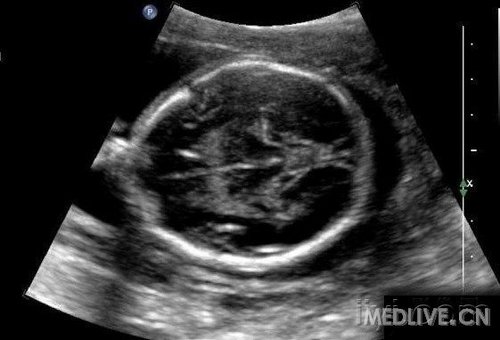

c.心脏